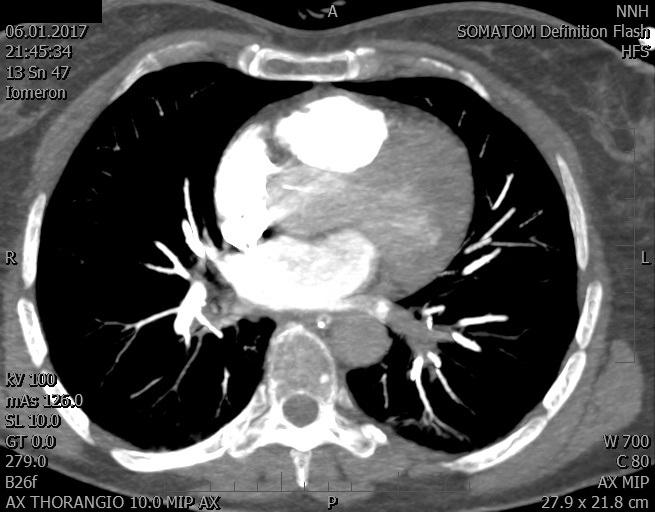

Video 1 - Akutní koronarografie prokázala normální nález na věnčitých tepnách s výjimkou suspekce na lehký spasmus na pravé koronární tepně.Echokardiograficky byla zjištěna těžká dysfunkce dilatované levé komory s nezvětšenou pravou komorou (video 2).

Video 2 - Echokardiograficky byla zjištěna těžká dysfunkce dilatační levé komory s nezvětšenou pravou komorou.Pro nejasnou příčinu zástavy jsme provedli i vyšetření výpočetní tomografií (CT), které vyloučilo plicní embolizaci (série 1 - soubory na konci článku). V den přijetí při přetrvávající oběhové nestabilitě byla nemocná opakovaně defibrilována pro fibrilaci komor se stabilizací rytmu po podání amiodaronu a mesocainu. Dle hemodynamických měření se jednalo o těžký kombinovaný šok. Vstupní laboratorní vyšetření bylo bez větších pozoruhodností. Posléze jsme doplnili anamnézu od příbuzných a zjistili, že pacientka užila do dvou hodin před srdeční zástavou první tabletu amoxicilinu na lehký respirační infekt. Při nevýtěžnosti vstupních vyšetření a nových anamnestických informacích jsme doplnili 14 hodin po kolapsu vyšetření koncentrace tryptázy v séru, která byla extrémně zvýšena (tabulka 2), což nás vedlo k podezření na anafylaxi.